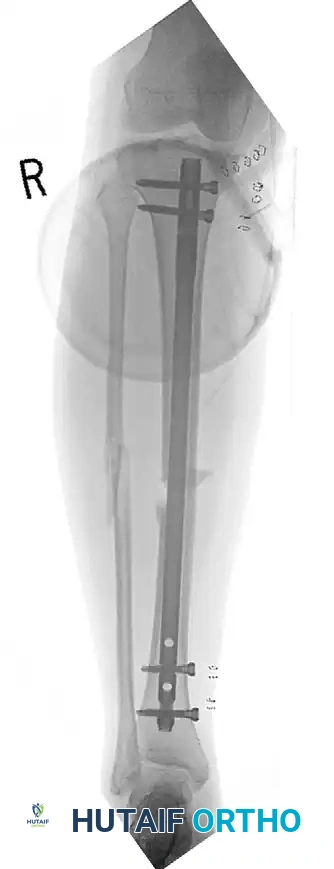

المسامير النخاعية لعظام الفخذ والساق

تدعم الأدلة الطبية الحديثة استخدام المسامير النخاعية المقفلة كعلاج مفضل لمعظم كسور الفخذ والساق. يتم إدخال مسمار معدني قوي داخل التجويف النخاعي للعظم لتثبيته من الداخل. أثبتت الدراسات أن التثبيت الفوري بالمسامير النخاعية، حتى في حالات الإصابة بالطلق الناري، يقلل من فترة البقاء في المستشفى ولا يزيد من معدلات العدوى إذا تم التنظيف الجراحي بشكل صحيح.

في حالات الكسور شديدة التلوث والدمار النسيجي، يطبق الأطباء مبدأ جراحة التحكم في الأضرار. يتم تثبيت الكسر مؤقتاً باستخدام مثبت خارجي حتى تتعافى الأنسجة الرخوة المحيطة، وبعد أسبوعين تقريباً، يتم تحويل التثبيت الخارجي إلى تثبيت داخلي دائم بالمسمار النخاعي.

النتيجة النهائية لتثبيت الكسر المفتوح وإنقاذ الطرف